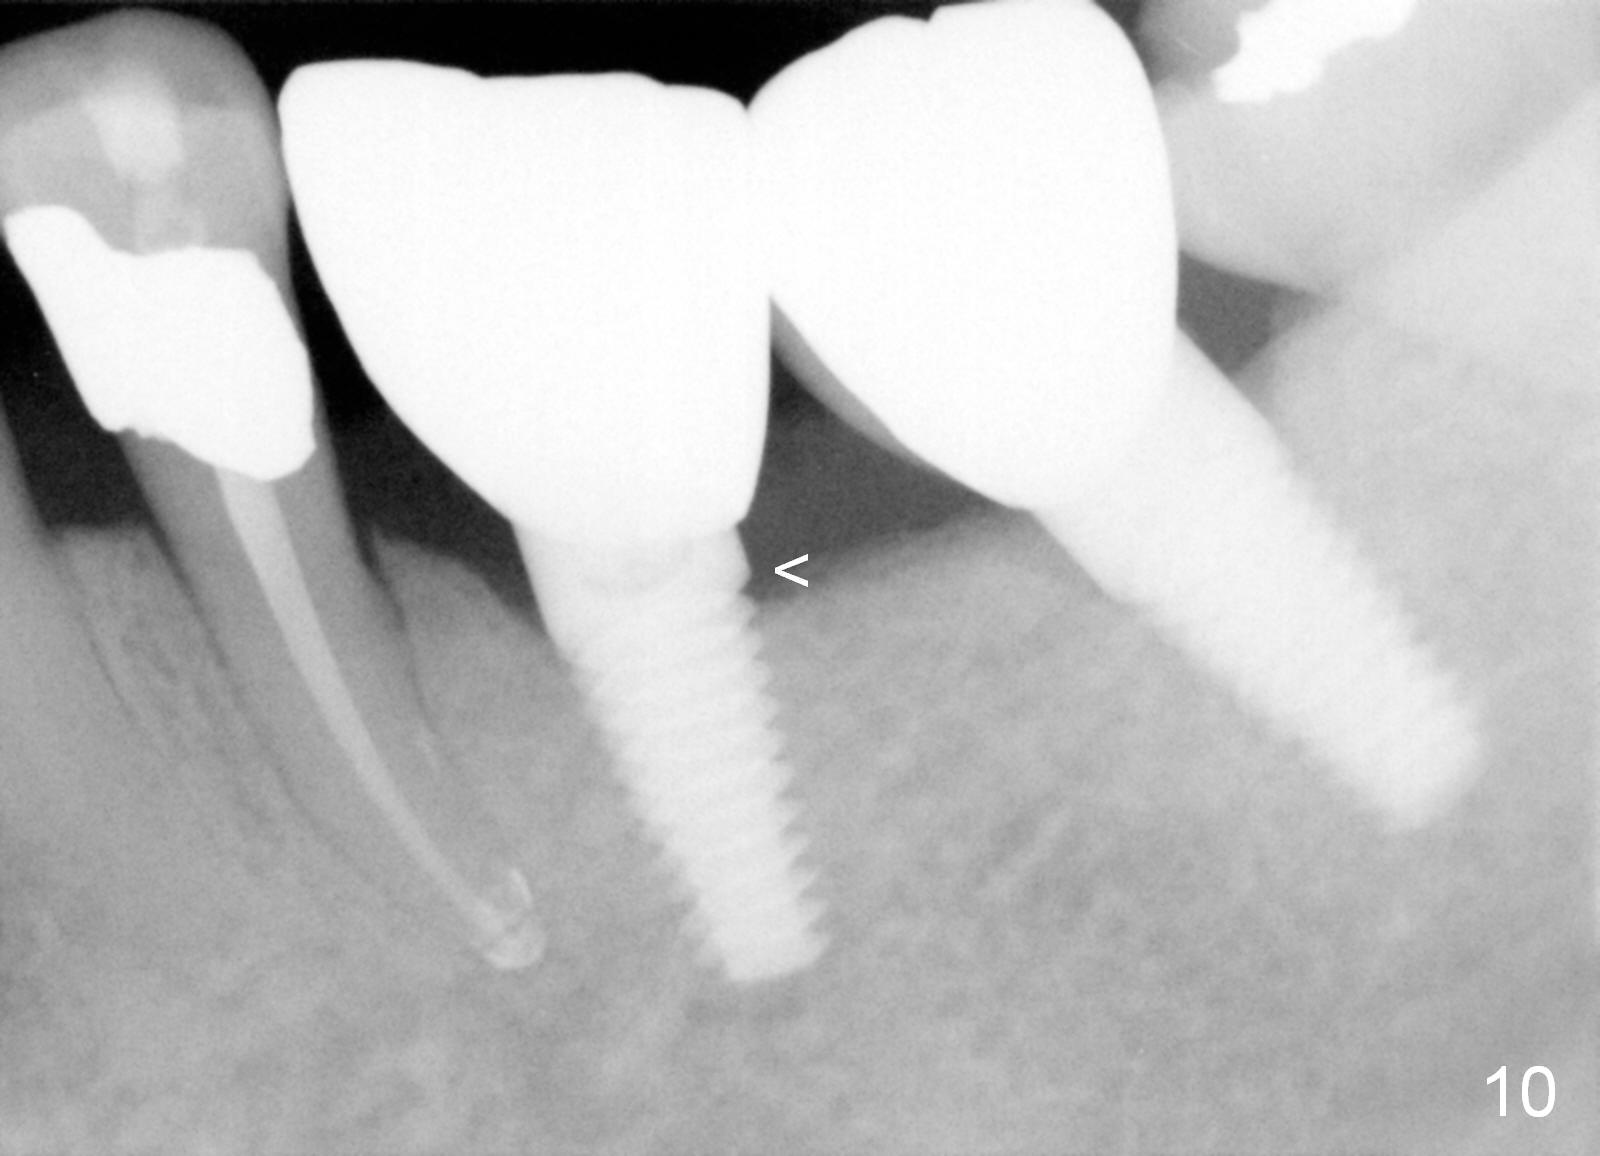

Three months postop, crestal bone has started to resorb (Fig.9 arrowheads). Resorption gets worse over time (Fig.10: 4 months post cementation, 11 months postop) (Fig.11: 1 year 2 month post cementation). On the other side (#30), postop bone resorption is not so severe. The patient's main concern is that she does not have normal taste ever since she got the implants.